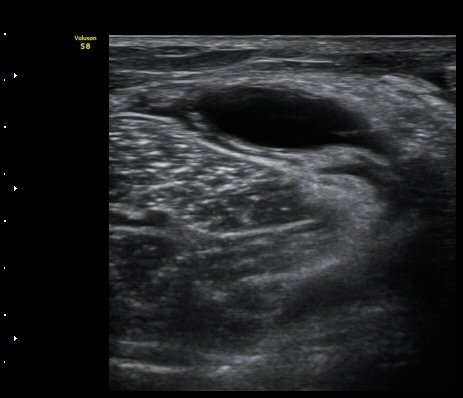

¹«¸ ¾Æ·¡ ÀåµýÁö Á¾´Ü¸é°Ë»ç¿¡¼ ÇÇÇÏ ¿¬ºÎÁ¶Á÷°ú ºñº¹±Ù »çÀÌ¿¡ ¼ö¾×Àú·ù(º£ÀÌÄ¿¾¾ ³¶Á¾ÀÌ ÅÍÁ®¼ Èê·¯³ª¿Â)°¡ °üÂûµÈ´Ù(»çÁø 4).

¹«¸ ¾Æ·¡ ÀåµýÁö Ⱦ´Ü¸é°Ë»ç¿¡¼ ÇÇÇÏ ¿¬ºÎÁ¶Á÷°ú ºñº¹±Ù »çÀÌ¿¡ ¼ö¾×Àú·ù(º£ÀÌÄ¿¾¾ ³¶Á¾ÀÌ ÅÍÁ®¼ Èê·¯³ª¿Â)°¡ °üÂûµÈ´Ù(»çÁø 5).

ÃÊÀ½ÆÄ À¯µµÇÏ º£ÀÌÄ¿¾¾ ³¶Á¾°ú º£ÀÌÄ¿¾¾ ³¶Á¾ ÆÄ¿·Î ¹ß»ýµÈ ³¶Á¾ ÈíÀÎ.